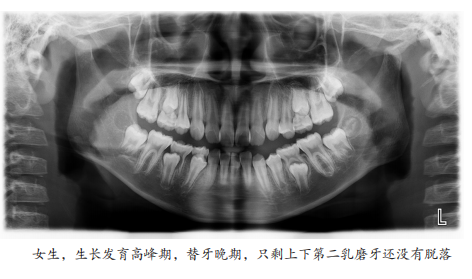

因此我们通过改变牙齿的位置,改变肌肉的力量,引导孩子自身的生长发育潜力,帮助孩子下颌尽最大可能生长好。我认为是在替牙的晚期,大概九岁或者十岁左右,这都算替牙晚期,在替牙晚期还没换完牙的时候,这个时候促进下颌骨生长会比较好。

当然每个孩子实际的身体的发育的年纪,跟岁数是不一样的,比如说我注意到有的孩子9岁就都换完牙了,有的孩子11岁还没换完牙,家长也可以以孩子上颌的2到2和下颌的2到2萌出后为参考,这也是早期矫正干预下颌后缩比较好的时期。

上下2-2萌出

理论上来讲男孩子的发育,要比女孩子要稍微晚一些,大概差1岁半到2岁之间,但临床上我们也观察到男孩们本身也有很大的一些差异性,相对来讲如果女孩早期矫正应该再提前一些,要比男孩子至少要早1到2年。